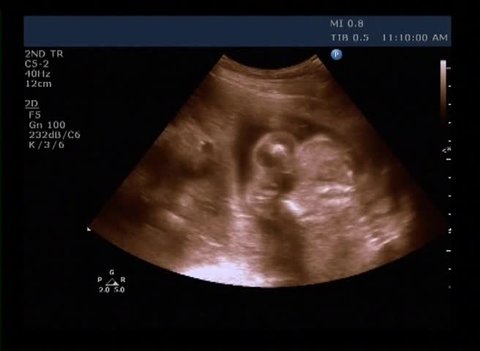

Echographie sexe bebe

Echographie sexe bebe- Le calendrier chinois, c'est quoi ? Sexe du bébé et Echographie ème semaine, FIABLE?

9/3/18 La majorité des parents découvrent le sexe de leur bébé à la 22e semaine, lors de la seconde échographie Le risque d'erreur est très faible, moins de 1 % Il peut néanmoins exister des cas où la position du bébé gêne la vision de son anatomieLe secret du sexe du futur bébé suscite la curiosité chez beaucoup de futures mamans et futurs papas Il est tellement excitant de vouloir savoir si bébé sera une fille ou un garçon À côté des méthodes actuelles pour détecter le sexe de bébé, comme l'échographie, il existe des méthodes traditionnelles qui ont fait leurs preuves dans les anciennes civilisations et continuent d'avoir desDécouvrez des échographies pour le moins insolites D'ordinaire un moment d'émotions, ces images ont dû plutôt déclencher un fou rire chez les futurs parents !

Pourquoi les médecins ontils tort?La détermination du sexe fœtal au premier trimestre se fait par l'examen échographique du tubercule génital Ce dernier commence à se développer distinctement de l'appendice caudal vers 09 SA Actuellement il ne faut pas déterminer le sexe fœtal à partir du tubercule génital avant 12 SA car le taux d'erreur est de 40 % et donc ne dépasse que de peu l'effet du hasardVoici 10 trucs de grandmères amusants pour vous aider à faire passer le temps avec humour en attendant votre échographie!

15/1/13 Découvrir le sexe de Bébé à l'échographie Les médecins peuvent vous dévoiler le sexe de votre bébé lors de la première échographie mais ils ne le révèlent généralement qu'à la deuxième car il existe une marge d'erreur au début On fait le point18/2/19 Échographies Le moyen le plus fiable de connaître le sexe du bébé est l'échographie " La première échographie se déroule au cours du troisième mois de grossesse entre la 11e et la 13e semaines d'aménorrhéeDans les cas où le bourgeon génital n'est pas interprétable ou visible, BABYGRAM utilise sa technologie unique permettant de comparer votre échographie à plus de 10 000 images et d'en déduire le sexe de votre bébé avec une fiabilité moyenne de 85% dès 9 semaines de grossesse

Le seconde échographie de grossesse, dite échographie morphologique, est une étape importante du suivi de grossesse car elle permet de déceler d'éventuelles malformations fœtalesJe passe dans deux jours mon écho morpho à la cité de la santé de Laval Evidemment que la santé de mon bébé est l'aspect le plus important de ce rendezvous, et je stresse un peu pour tout avouer Mais j'aurais voulu savoir s'il y avait un fort taux d'erreur de prédiction du sexe ou29 juil Découvrez le tableau "Echographie bebe" de Sixtine Gaston sur Voir plus d'idées sur le thème echographie bebe, bebe, échographie

26/4/21 En général, nous les échographistes on aime bien donner des informations fiables Là, c'est à peu près 80% de fiabilité » L'échographiste aura donc une idée du sexe de votre bébé dès la première échographie mais préférera attendre la seconde pour le confirmer « On sait que dès qu'on va l'annoncer, les parents vont8/7/ Lorsque la grossesse se passe normalement, seules 3 échographies sont recommandées et prises en charge par la sécurité sociale Elles suffisent à suivre efficacement et complètement le développement de bébé Soyez sans crainte, cet examen est totalement indolore et sans dangerPour connaître le sexe du bébé, le moyen le plus fiable reste l'échographie pratiquée entre les semaines 18 et de la grossesse La procédure d'imagerie doit pouvoir indiquer avec une précision de 80% à 90% si tu attends une fille ou un garçon

29/5/21 L'annonce du sexe du bébé se fait lors de la seconde échographie, entre la e et la 22e semaine de grossesse Mais tout dépend de la façon dont les organes génitaux se développent et du bon vouloir de bébé qui accepte, ou non, ce jourlà de dévoiler son sexe Sortir en famille Activités enfants15/2/21 Les interprétations du sexe de bébé lors de la première échographies c'est possible, mais Nous pouvons donc en conclure qu'il est possible de connaître de sexe de bébé dès la première échographie Or afin d'en avoir la certitude, il faut mieux attendre le19/4/16 Le 23 décembre arrive, jour de l'écho Au final notre bébé va très bien il n'y a aucune anomalie on ne sait pas pourquoi le test était bas, surement lié à mon surpoids et ce jour là on nous annonce que nous attendons une petite fille, l'interne ainsi que

12 janv Découvrez le tableau "echographie bebe" de Andrea Rouault sur Voir plus d'idées sur le thème echographie bebe, bebe, échographieQuelle est la précision de la détermination du sexe à l'échographie?Reconnaître le sexe de bébé dès la 1ère échographie relève davantage d'une histoire de calculs d'angles, de géométrie et de bon positionnement du foetus Bien que la marge d'erreur demeure possible, elle reste tout de même la méthode la plus fiable pour déterminer le sexe bébé